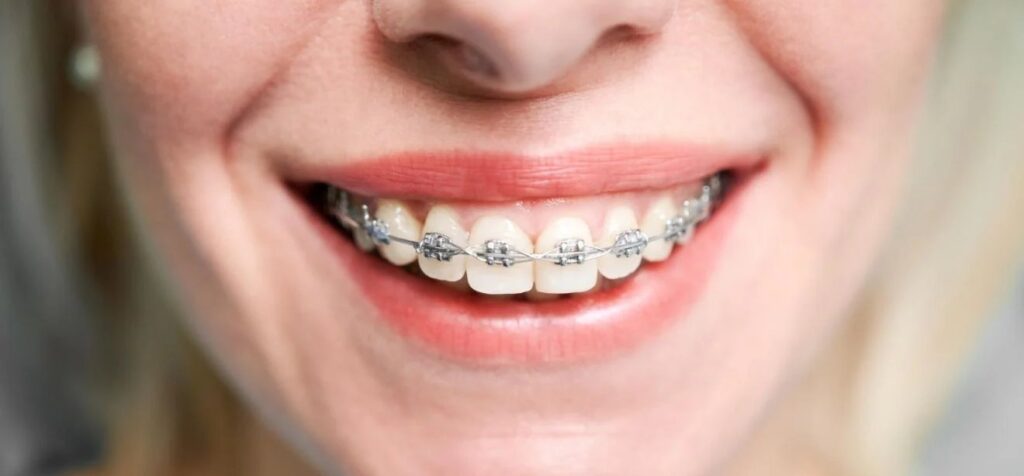

Conseguir atendimento ortodôntico gratuito ou a preços reduzidos ainda é um obstáculo para muitas famílias capixabas. Embora o Sistema Único de Saúde (SUS) ofereça serviços odontológicos, o tratamento com aparelho é limitado a poucos centros especializados, com filas de espera extensas.

Levantamentos nacionais revelam que cerca de 62% das crianças e adolescentes apresentam algum grau de má oclusão — desalinhamento dos dentes ou encaixe inadequado das arcadas. Em estudos com escolares, a prevalência chega a 68%, indicando que a maioria dos menores poderia se beneficiar de avaliação ortodôntica.

Os problemas mais comuns incluem:

- dentes apinhados, por falta de espaço na arcada;

- mordida cruzada, quando os dentes inferiores ficam à frente dos superiores;

- mordida aberta, situação em que os dentes da frente não se tocam ao fechar a boca.

Além do impacto estético, essas alterações podem prejudicar mastigação, fala e articulação da mandíbula. Profissionais recomendam a primeira avaliação por volta dos seis ou sete anos, fase em que dentes de leite e permanentes coexistem e o crescimento ósseo ainda pode ser direcionado.

Imagem: Freepik